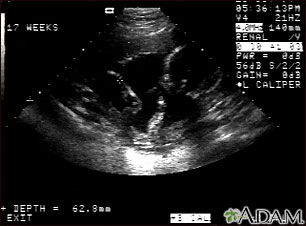

This is a normal fetal ultrasound performed at 17 weeks gestation. This is the type of image pregnant mothers may see on the ultrasound screen, or that the technician may print. It shows the head on the right, and the cross hair pointing to the left ankle. The left leg and arm are visible in the center of the screen.